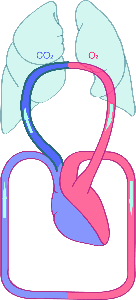

Detailreiche Fotografien aus der medizinischen Praxis ergänzen die Texte; moderne, genaue,

wissenschaftliche Zeichnungen geben Einblick in die Anatomie und die Funktion der Lunge und

anderer Organe.